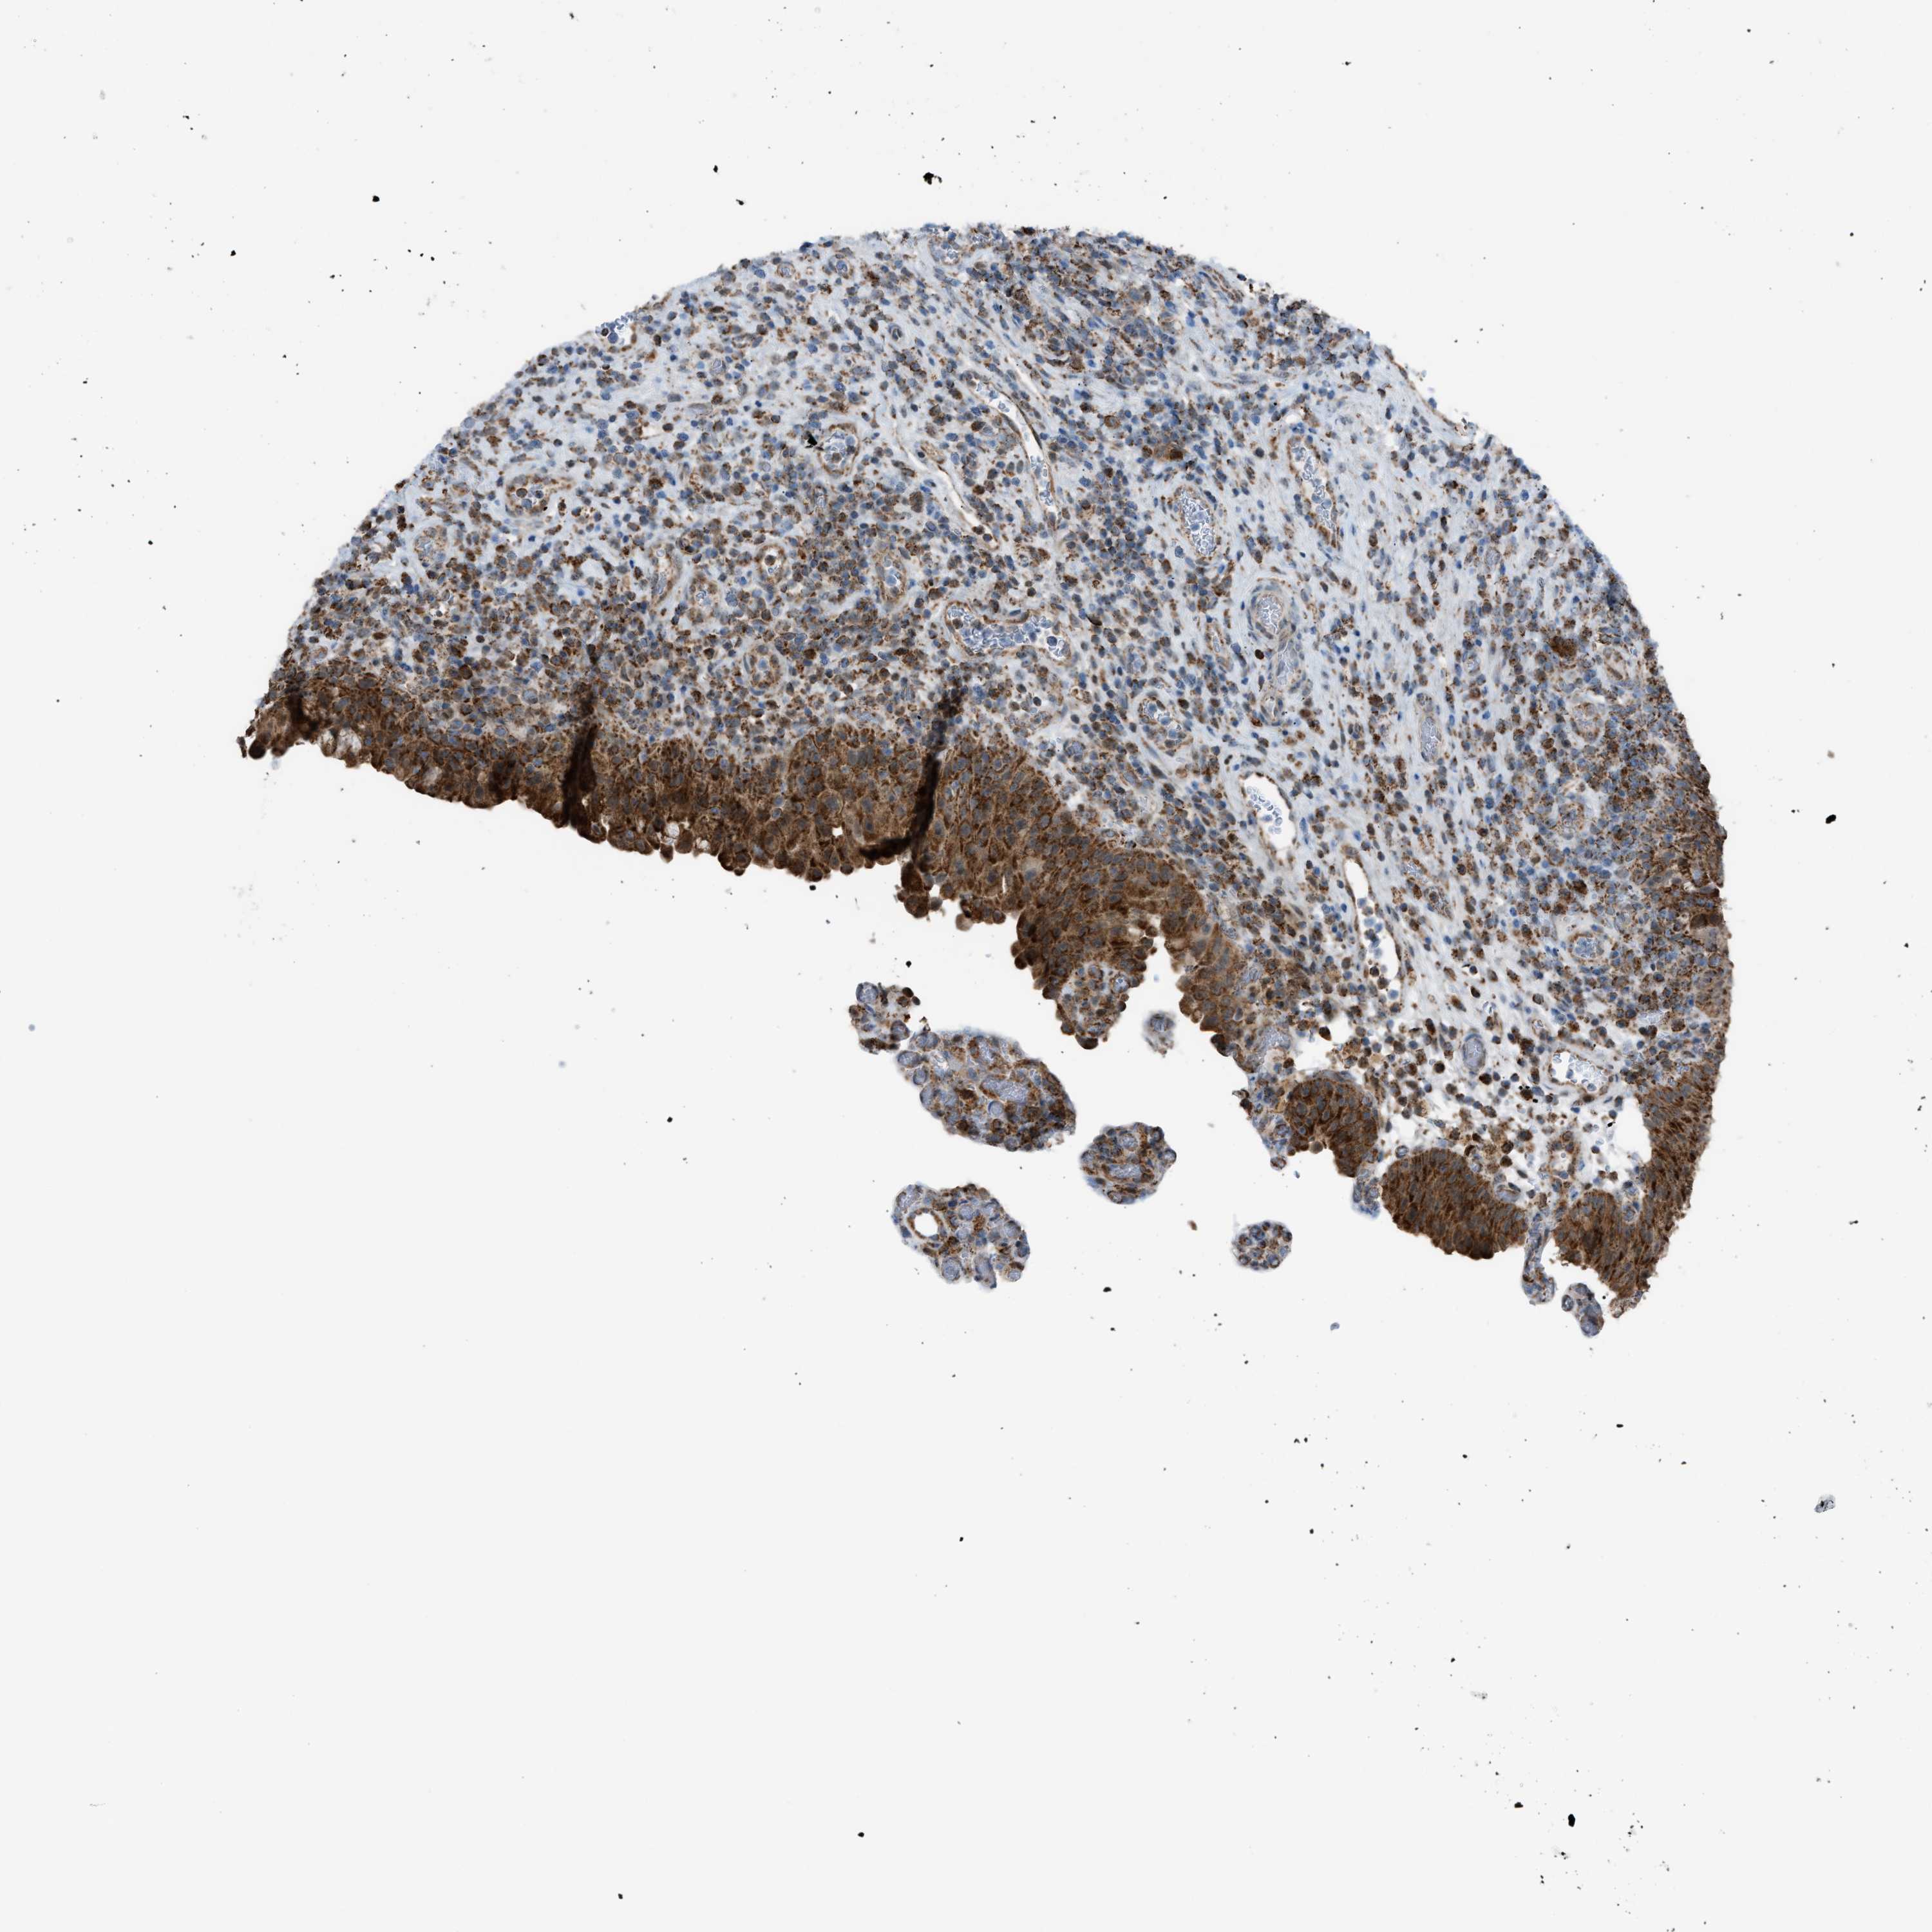

UROTHELIAL CANCER - Protein expressioni

A mouse-over function shows sample information and annotation data. Click on an image to view it in a full screen mode. Samples can be filtered based on level of antibody staining by selecting one or several of the following categories: high, medium, low and not detected. The assay and annotation is described here.

Note that samples used for immunohistochemistry by the Human Protein Atlas do not correspond to samples in the TCGA dataset.

Antibody stainingi

Antibody staining in the annotated cell types in the current human tissue is reported as not detected, low, medium, or high, based on conventional immunohistochemistry profiling in selected tissues. This score is based on the combination of the staining intensity and fraction of stained cells.

Each image is clickable and will lead to virtual microscopy that enables deeper exploration of all samples and also displays staining intensity scores, fraction scores and subcellular localization as well as patient and tissue information for each sample.

Antibody HPA015746

Staining

High

Medium

Low

Not detected

Intensity

Strong

Moderate

Weak

Negative

Quantity

>75%

75%-25%

<25%

None

Location

Nuclear

Cytoplasmic/membranous

Cytoplasmic/membranous,nuclear

Urothelial carcinoma, Low grade

Urothelial carcinoma, High grade